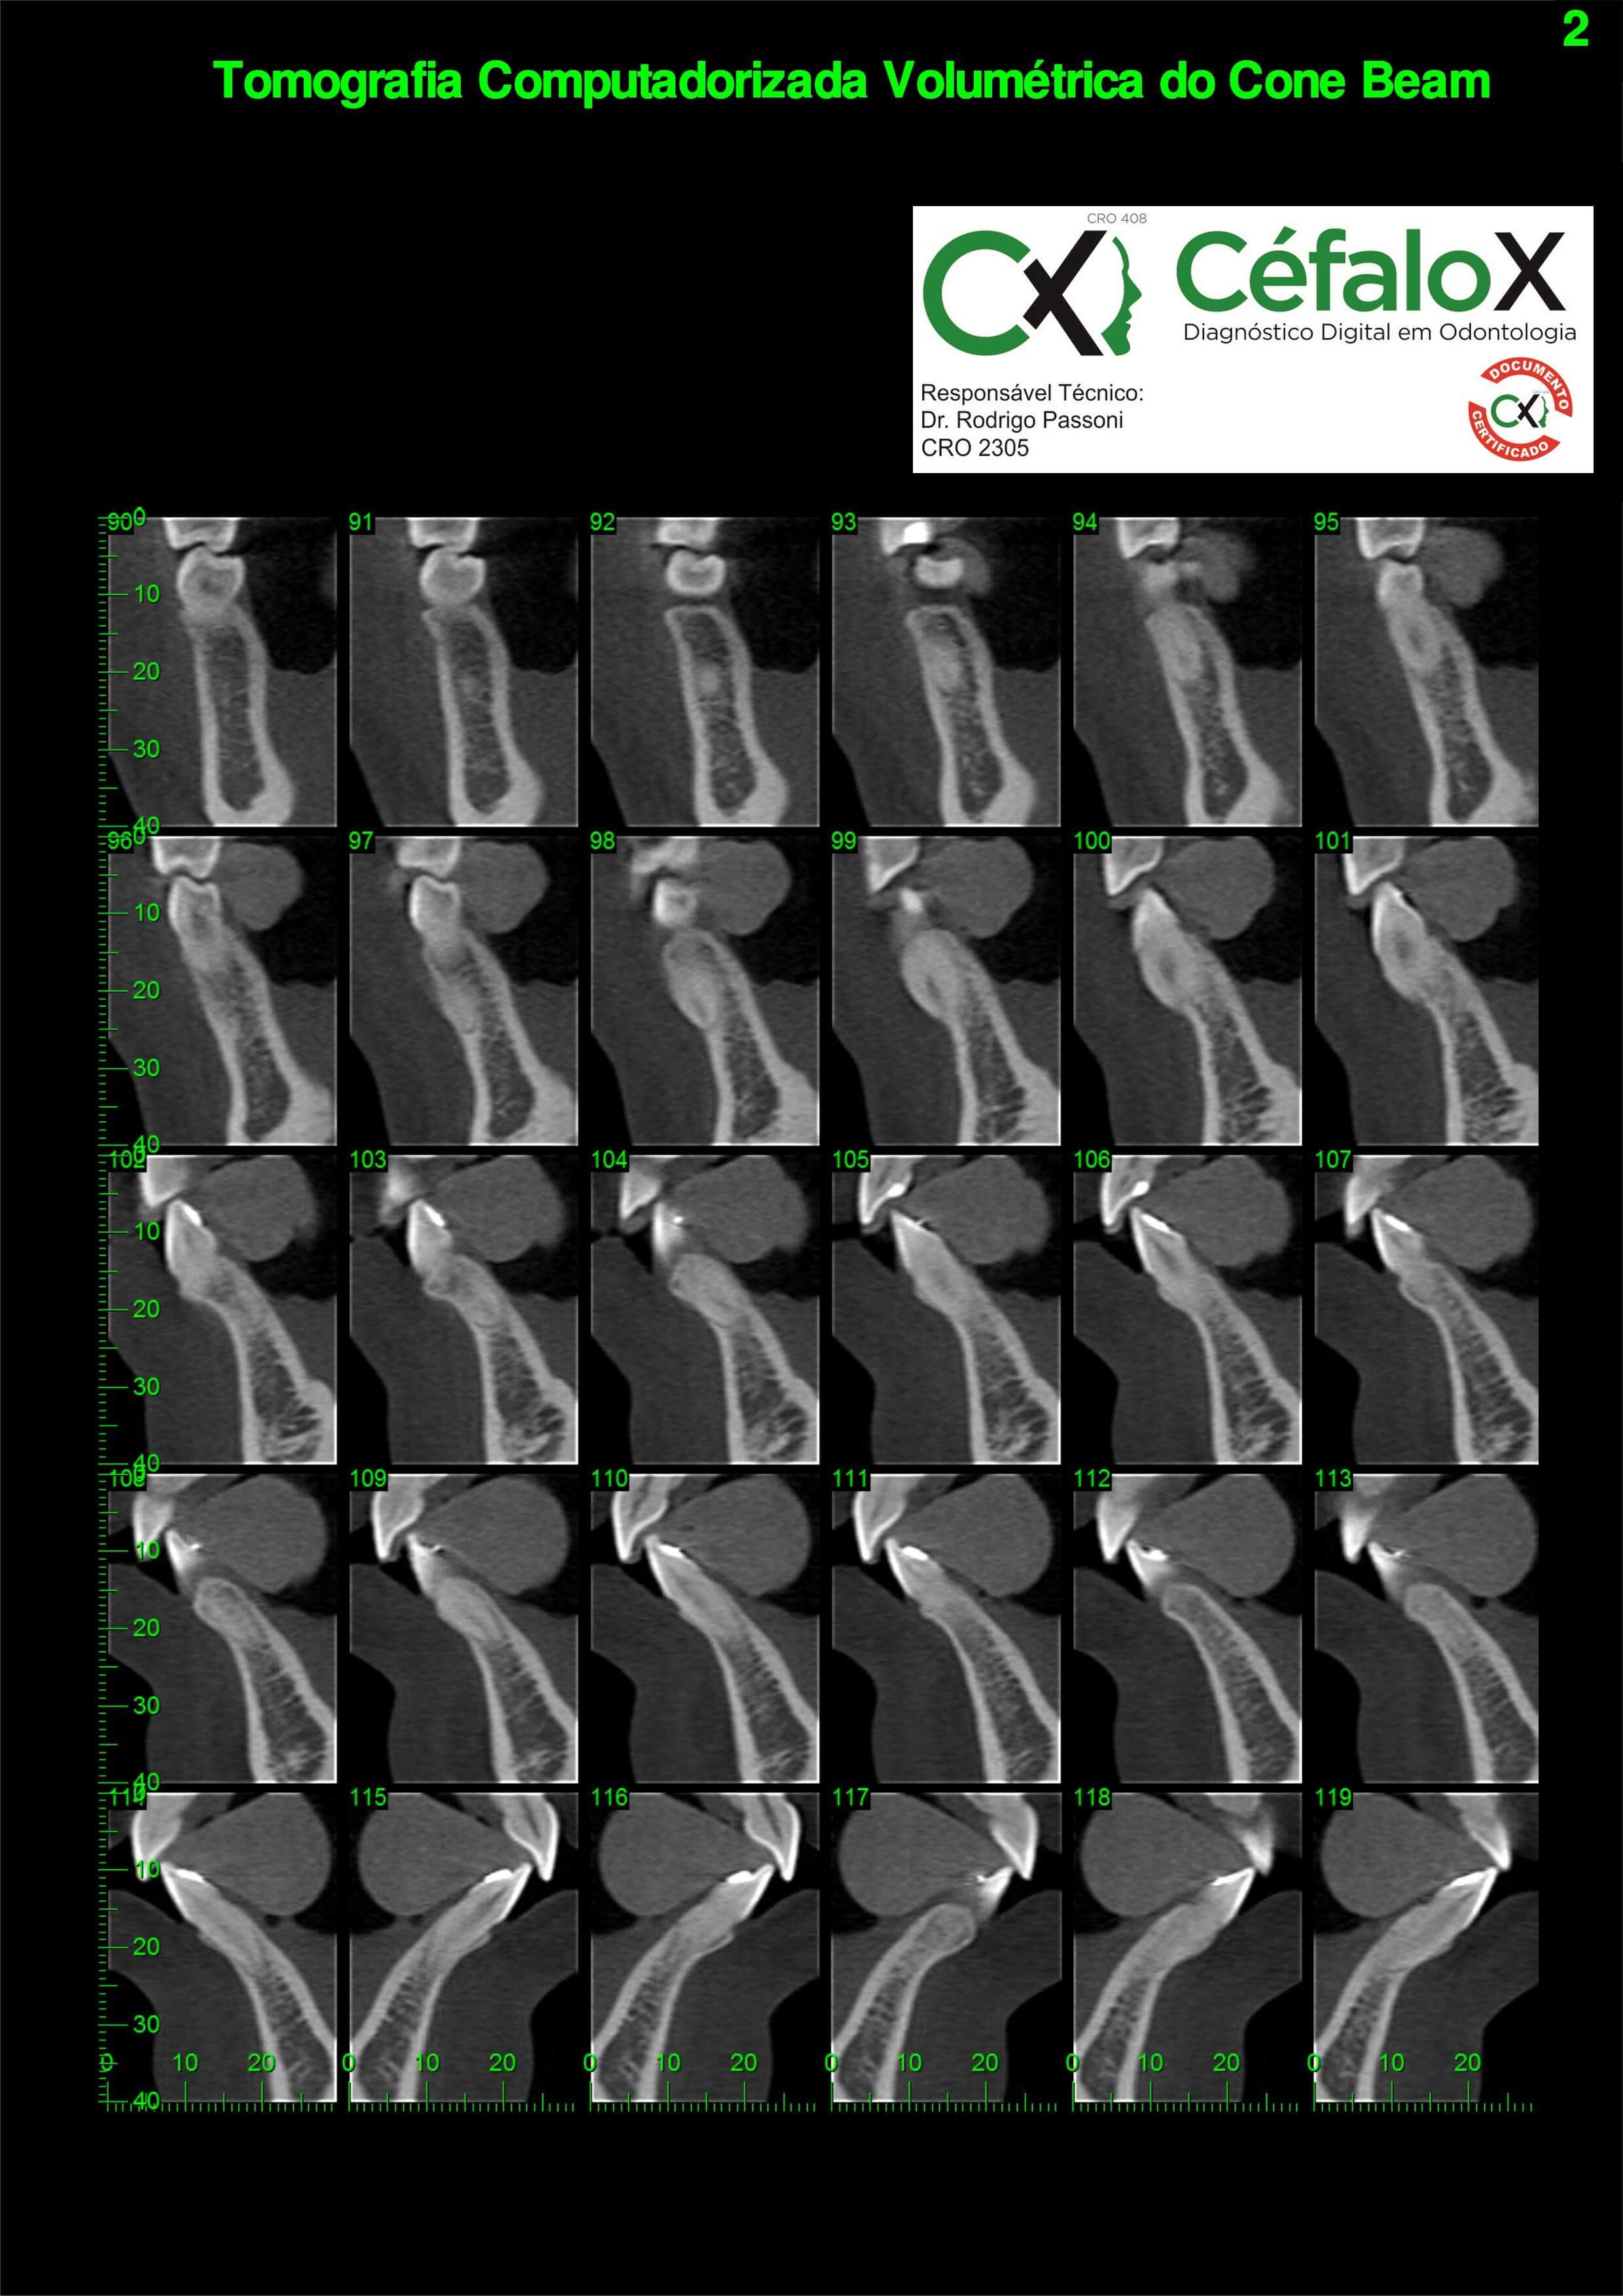

TC de face (do Hióide à Glabela), reconstruções 3D do tecido mole/ósseo/vias aéreas, radiografia panorâmica, telerradiografia lateral e frontal com traçado, cortes transversais e axial de maxila/mandíbula, ATM e arquivo DICOM – entregue em pasta e caixa de Pvc.